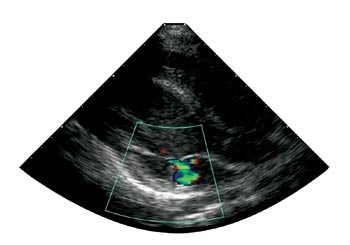

Etter ett år med enzymsubstitusjon kunne guttene spille fotball og stå på ski uten problemer. De hadde ikke kunnet seponere karbamazepin, men var lite plaget med smerter og hadde ikke lenger diaré. Sommeren 2002 kunne de for første gang på flere år bade i sjøen uten å få smerter. Jevnlige kontroller av globotriaosylceramid i plasma og i urinsediment har vist markant reduksjon av avleiringsproduktet (tab 1). Ekkokardiografi og EKG har ikke vist signifikante endringer, bortsett fra at det hos pasient 1 har utviklet seg en liten mitralinsuffisiens (fig 2). Cerebral MR viser fortsatt normale funn hos pasient 1. Hos pasient 2 er det ingen nytilkomne lesjoner, og T2-signalintensiteten er lett redusert fra første undersøkelse.

Hjertesykdom debuterer vanligvis i 30 – 40 års alder med konsentrisk hypertrofi av venstre ventrikkel med bevart systolisk funksjon (18). Det er vist at opptil 4 % av menn med hypertrofisk kardiomyopati kan ha Fabrys sykdom (19). Forkortet PR-intervall og abnorm atrioventrikulær overledning samt lett grad av lekkasje over mitral- og aortaklaffen, er også velkjent (20). Begge våre pasienter har moderat hypertrofisk venstre ventrikkel av eksentrisk type og et PR-intervall på 130 ms, som er i nedre normalområdet. I tillegg er pasient 1 relativt bradykard med hvilepuls på 40 – 45 slag/minutt. Ved siste undersøkelse fikk han påvist mitralinsuffisiens grad 1, et funn som kan være oversett ved undersøkelser før enzymsubstitusjonsbehandlingen. Alle disse funnene må imidlertid tolkes som tidlig kardial manifestasjon av Fabrys sykdom.